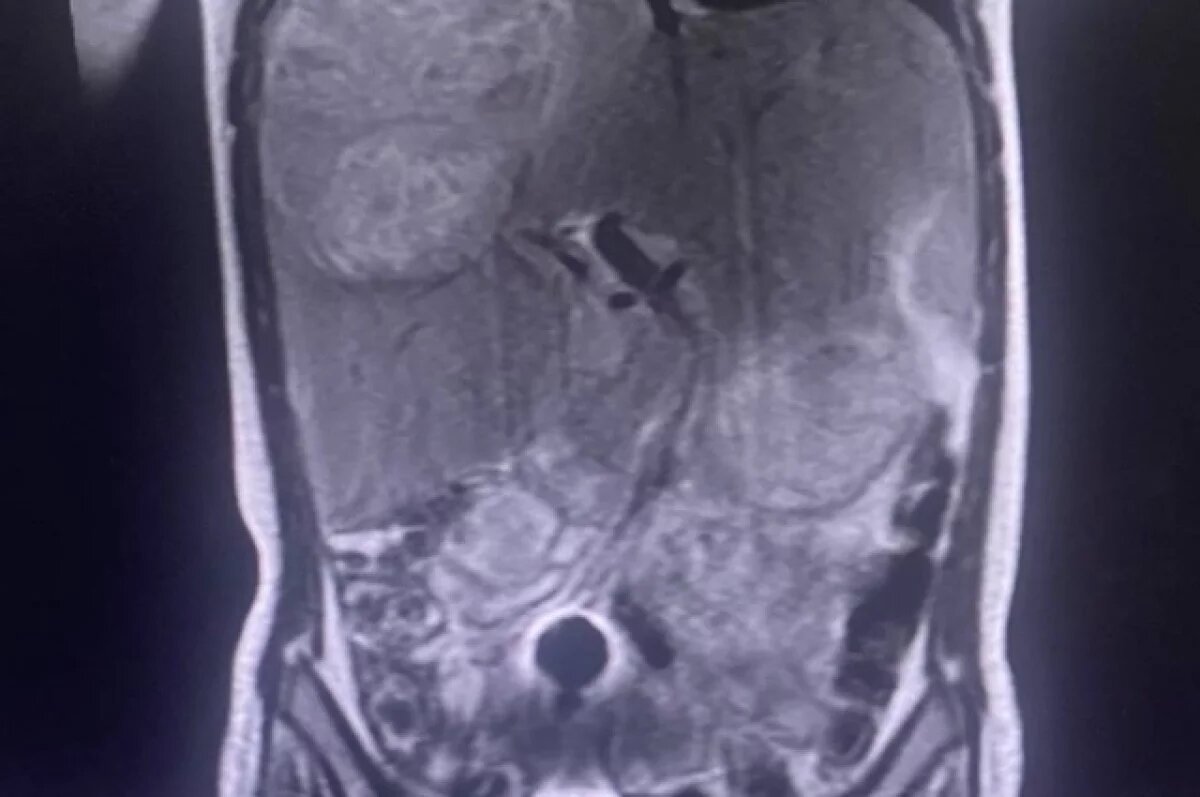

После госпитализации в ЧОДКБ был диагностирован многокамерный абсцесс правой доли печени размером 10-12 см, который поразил три из четырёх сегментов и сдавливал окружающие органы. Врачи приняли решение о проведении уникальной операции — удалении правой доли печени без вскрытия абсцесса, так как стандартная пункция в данном случае была бы неэффективна.